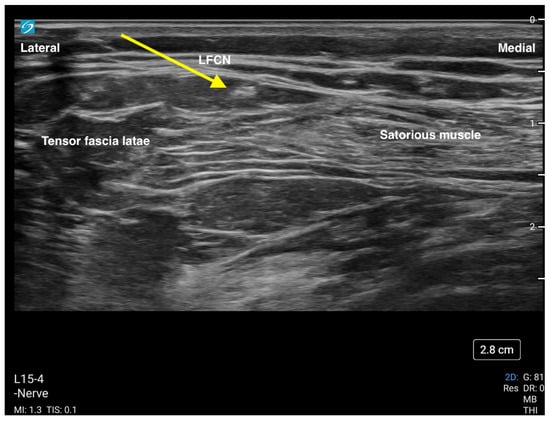

The lateral femoral cutaneous nerve (LFCN) block is a useful adjunct to the other nerves (femoral nerve, FICB) commonly blocked for hip fracture surgery. Its distribution at the lateral side of the leg allows for easier blockade in the context of a lateral surgical incision. The LFCN is indicated for analgesia for surgery of the anterolateral thigh, i.e., open reduction internal fixation of the hip, hip arthroplasty and/or hemiarthroplasty, muscle biopsy, and to treat meralgia paresthetica. The block is performed using a high-frequency linear ultrasound probe placed in a transverse position just distal to the anterior superior iliac spine (ASIS). The nerve can be identified as a hyperechoic structure superficially and between the sartorius and tensor fascia latae muscles (Figure 5). Depositing 3–5 mL of local anesthetic by inserting a needle using an in-plane approach and deep to the fascia lata should provide good analgesic coverage of the lateral thigh.

Figure 5. This is an ultrasound image of the lateral femoral cutaneous nerve (LFCN). The yellow arrow is pointing to the nerve. The nerve is blocked with a needle in the direction from lateral to medial.